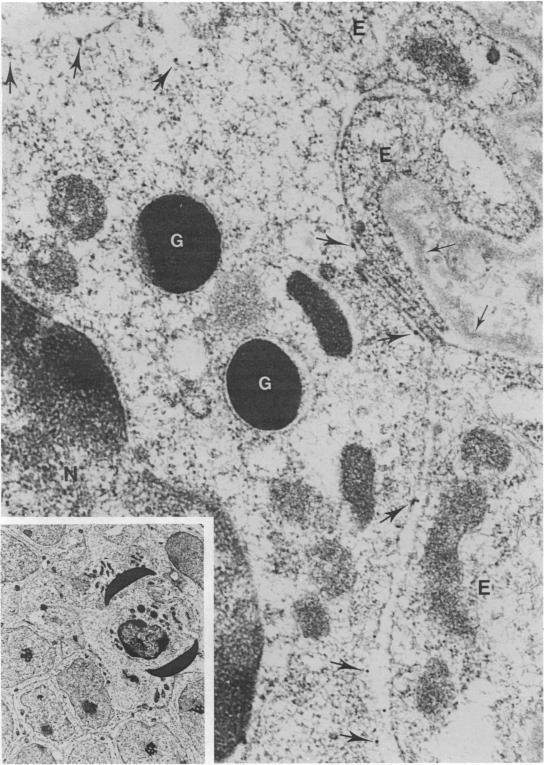

A panel of monoclonal antibodies was used to define the lymphocyte subpopulations in the sheep uterus at various stages of the oestrous cycle. A striking finding was that the majority of lymphocytes in the uterine and endometrial glandular epithelia belonged to a unique lymphocyte subpopulation that expressed the CD45R antigen but was negative for major histocompatibility complex (MHC) class II molecules and expressed low or undetectable levels of the CD5 antigen. When examined under the electron microscope using the immunogold technique, the CD45R+ lymphocytes were found to have one to three membrane-bound granules in their cytoplasm. Other lymphocyte subpopulations found in the uterus at various stages of the oestrous cycle were localized mainly in the caruncular and intercaruncular stroma. The unique CD45R+ granular lymphocyte subpopulation may be equivalent to the 'natural killer' cells reported in mouse and man, and may have an important role in local immunity of the female reproductive tract.

一组单克隆抗体被用于确定发情周期不同阶段绵羊子宫中的淋巴细胞亚群。一个显著的发现是,子宫和子宫内膜腺上皮中的大多数淋巴细胞属于一个独特的淋巴细胞亚群,该亚群表达CD45R抗原,但主要组织相容性复合体(MHC)II类分子呈阴性,且CD5抗原表达水平低或检测不到。当使用免疫金技术在电子显微镜下检查时,发现CD45R+淋巴细胞的细胞质中有一到三个膜结合颗粒。在发情周期不同阶段子宫中发现的其他淋巴细胞亚群主要位于肉阜和肉阜间基质中。独特的CD45R+颗粒淋巴细胞亚群可能等同于在小鼠和人类中报道的“自然杀伤”细胞,并且可能在女性生殖道的局部免疫中发挥重要作用。